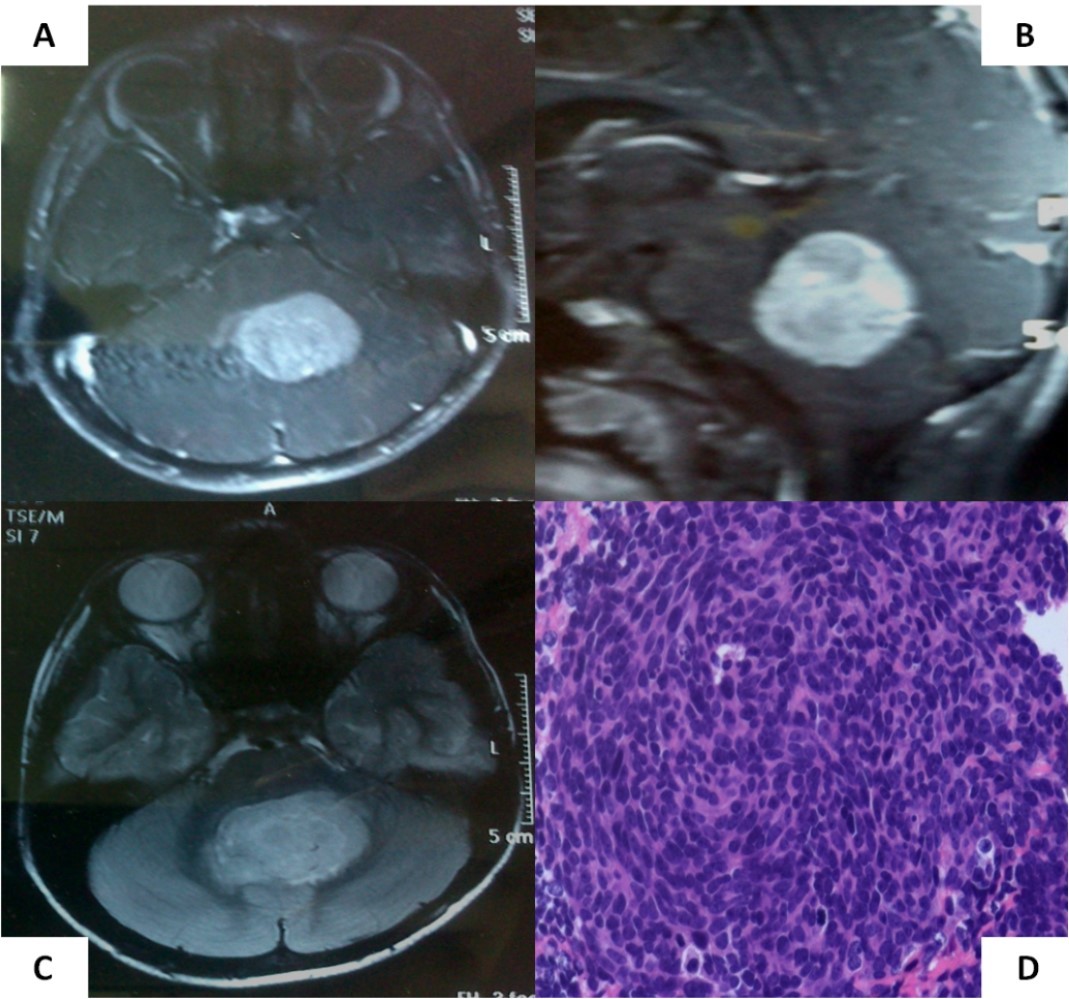

A 6-year old boy initially presented to us with headache, vomiting, and ataxia of 6-months duration. Cranial magnetic resonance imaging (MRI) showed a large lobulated, midline vermian space-occupying lesion, hypo-to iso-intense on T1-weighted images, hyperintense on T2-weighted and FLAIR images with prominent and homogenous enhancement post-contrast (Figure 1A-C) with aqueductal compression causing supratentorial hydrocephalus suggestive of medulloblastoma. He underwent near-total excision of the vermian space occupying lesion at an outside hospital that was reported as classical medulloblastoma on conventional light microscopy (Figure 1D). The non-availability of formalin-fixed paraffin embedded tumor tissue blocks precluded further molecular subgrouping of medulloblastoma. Post-operative MRI revealed the presence of two small residual enhancing nodules at the edge of the resection cavity. Neuraxial staging using MRI of the spine with gadolinium and cerebrospinal fluid (CSF) malignant cell cytology via a lumbar puncture did not show any evidence of leptomeningeal dissemination. Although there was no evidence of leptomeningeal metastases (M0 status), he was categorized as high-risk disease by virtue of residual tumor volume >1.5 X 1.5cm2 as per the prevalent risk-stratification system, and treated on an ongoing institutional phase II study of concurrent carboplatin with standard-dose craniospinal irradiation with posterior fossa boost followed by six cycle of multi-agent adjuvant systemic chemotherapy. Neuraxial imaging after completion of adjuvant therapy showed complete resolution of residual enhancing nodules with reactive gliosis.

Figure 1.Pre-operative MRI of the brain showing a brilliantly enhancing midline vermian lesion in axial (A) and sagittal (B) T1-weighted post-contrast images with variable intensity on T2-weighted images (C). Photomicrograph of the tumor (D) showing it highly cellular tumor composed of small blue round cells consistent with classic medulloblastoma (X 400, hematoxylin & eosin)

Pre-operative MRI of the brain showing a brilliantly enhancing midline vermian lesion in axial (A) and sagittal (B) T1-weighted post-contrast images with variable intensity on T2-weighted images (C). Photomicrograph of the tumor (D) showing it highly cellular tumor composed of small blue round cells consistent with classic medulloblastoma (X 400, hematoxylin & eosin)